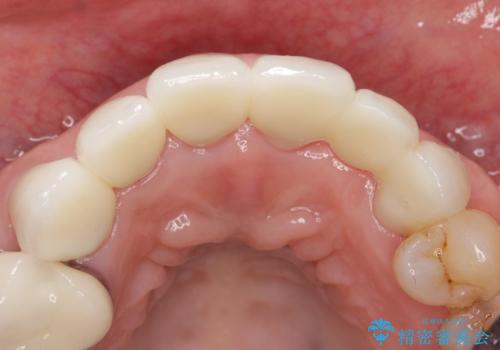

金属を使わないジルコニアセラミッククラウンの自然な仕上がりにご満足頂けました。

被せ物の種類:ジルコニアセラミッククラウン スタンダード